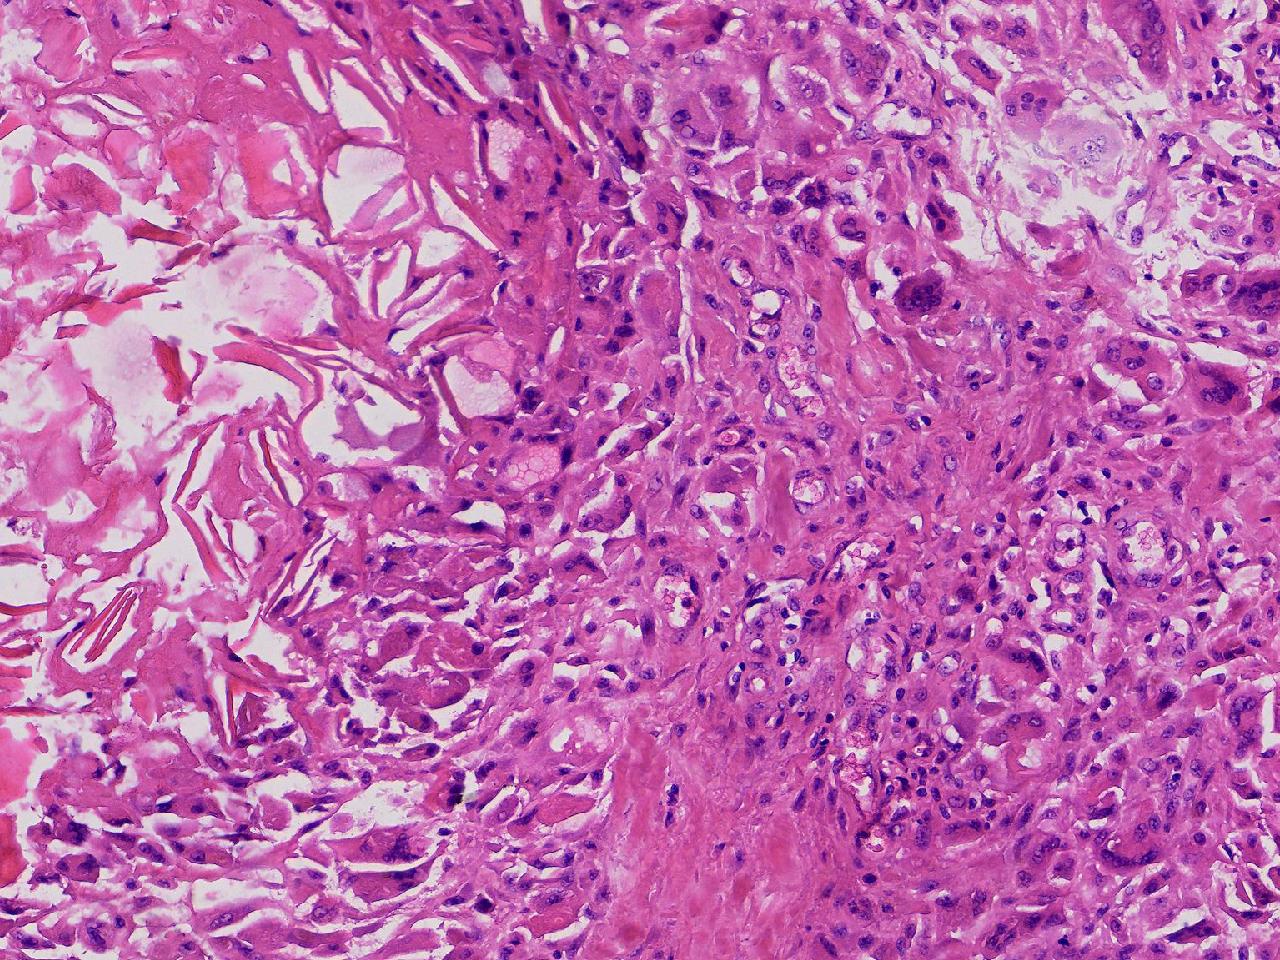

皮样/表皮样囊肿伴周边异物巨细胞反应?

右侧臀部皮下肿物10余年,渐增大,无破溃,无疼痛。

右侧臀部皮下肿物

囊性肿物一个,直径2.5厘米,肿物位于皮下。

异物肉芽肿性炎?

表皮样囊肿伴异物肉芽肿性炎。